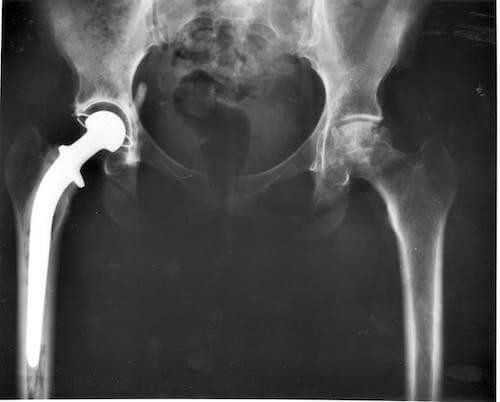

Weterynarz będzie odpowiedzialny za zbadanie stawów biodrowych, a badanie rentgenowskie w okolicy miednicy pozwoli zidentyfikować problem. Po zdiagnozowaniu istnieją różne metody leczenia w celu złagodzenia objawów i zapobiegania dalszemu postępowi. Jak dotąd nie ma lekarstwa na dysplazję stawu biodrowego u kotów.

Leczenie może obejmować fizykoterapię, ograniczenie aktywności, stosowanie doustnych lub wstrzykiwanych leków przeciwzapalnych, kontrolę masy ciała. A w bardziej zaawansowanych przypadkach operację, która może nawet obejmować wymianę całego stawu biodrowego.